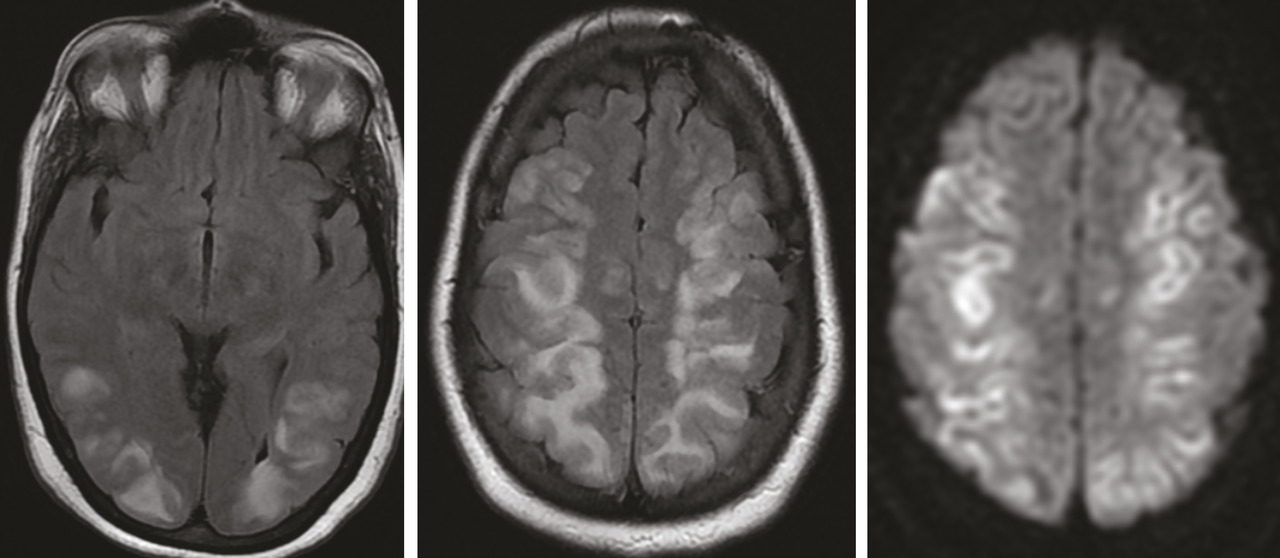

Encéphalopathie postérieure réversible

Siham Nasri, Mohammed Joudar

Cette femme de 36 ans avait une hypertension artérielle à 200/100 mmHg et une monoparésie du membre supérieur gauche post-critique, dans le cadre d’une toxémie gravidique. Une IRM encéphalique mettait en évidence des anomalies de signal cortico-sous-corticales et profondes, bilatérales et...